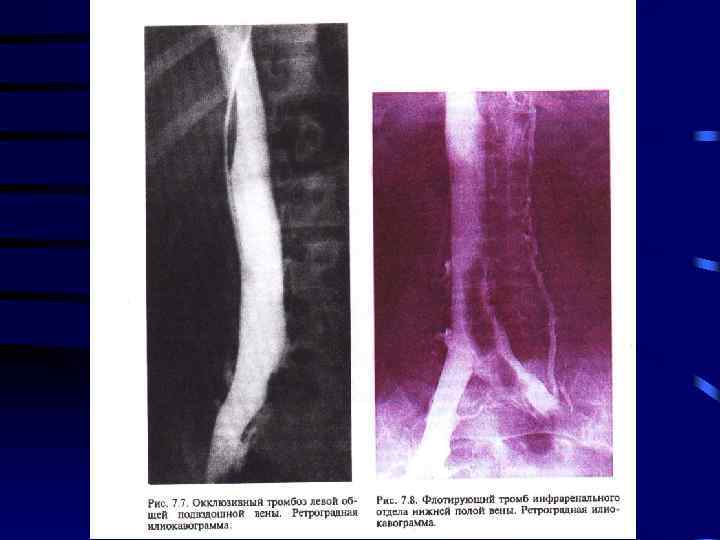

Диагностика: 1. Клиника 2. УЗИ сосудов 3. Дуплексное сканирование 4. Флебография

Лечение: 1. Консервативная терапия: a) Эластическое бинтование с возвышенным положением b) Гепарин c) Антибиотики d) Покой 5 -7 суток 2. При флотирующем или эмбологенном тромбозе хирургическое лечение: a) Установка Кава-Фильтра b) Пликация вен выше места тромба